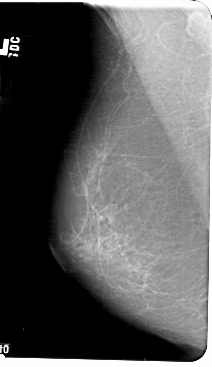

A_1405_1.LEFT_MLO

LEFT_MLO LINES 5491 PIXELS_PER_LINE 3166 BITS_PER_PIXEL 12 RESOLUTION 43.5 NON_OVERLAY